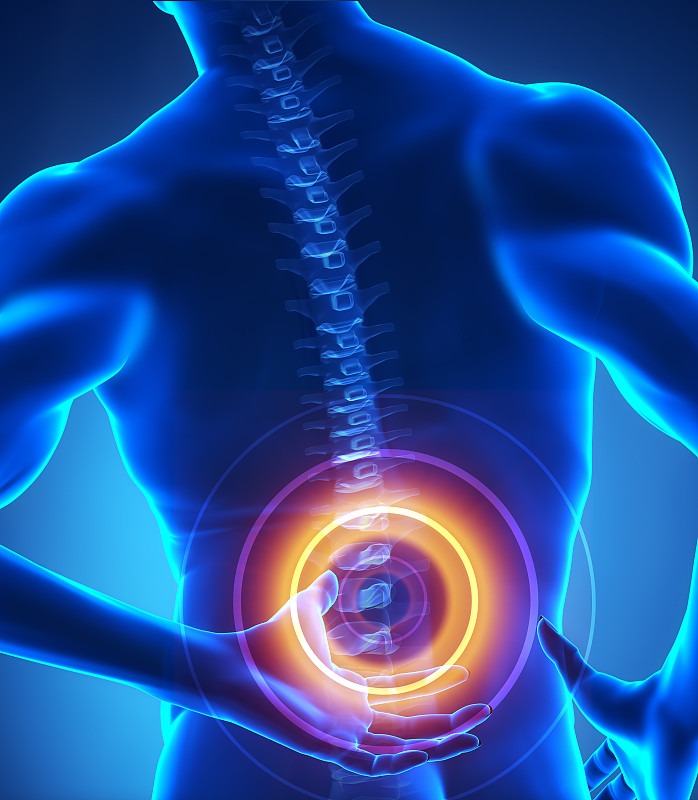

腰背部疼痛。详情

腰背部疼痛。详情

腰背部疼痛。详情